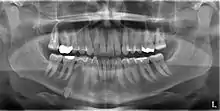

An impacted tooth is one that fails to erupt into the dental arch within the expected developmental window. Because impacted teeth do not erupt, they are retained throughout the individual's lifetime unless extracted or exposed surgically. Teeth may become impacted because of adjacent teeth, dense overlying bone, excessive soft tissue or a genetic abnormality. Most often, the cause of impaction is inadequate arch length and space in which to erupt. That is the total length of the alveolar arch is smaller than the tooth arch (the combined mesiodistal width of each tooth). The wisdom teeth (third molars) are frequently impacted because they are the last teeth to erupt in the oral cavity. Mandibular third molars are more commonly impacted than their maxillary counterparts.

Classifications enable the oral surgeon to determine the difficulty in removal of the impacted tooth.[9] The primary factor determining the difficulty is accessibility, which is determined by adjacent teeth or other structures that impair access or delivery pathway. The majority of classification schemes are based on analysis on a radiograph. The most frequently considered factors are discussed below.